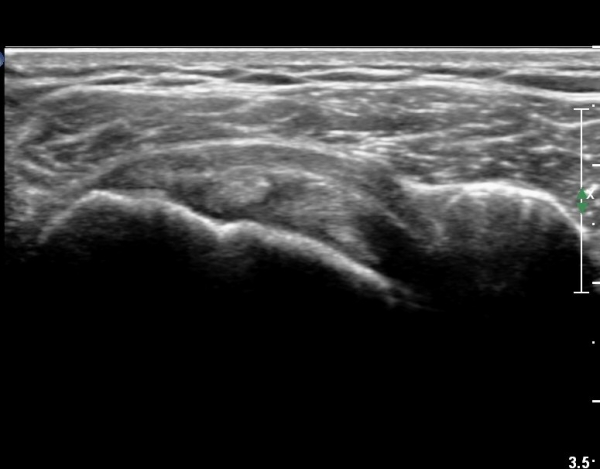

±Ø»ó°Ç Á¶´ã¸é°Ë»ç¿¡¼­ ±Ø»ó°ÇÀÇ ÅðÇ༺º¯È­È­ ºÎºÐÀûÀÎ ÆÄ¿­ÀÌ  °üÂûµÇ¸é ´ë°áÀýÀº

ºñÈĵǾî ÀÖ´Ù(»çÁø 6, 7, 8).